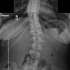

Submitted by LaisyDucky t3_119lnjt in mildlyinteresting

My wife has severe congenital scoliosis - a case bad enough her x-rays could be found in medical books. At 14, she had her spine fused from C4 to her sacrum with stainless steel rods(basically everything except her neck bones, for those who don't know). Her surgery was the second of its kind, the first being on a much less severe case, and hers was considered a success. Said rods were removed when she was 18 which she was fortunate enough to be able to keep.